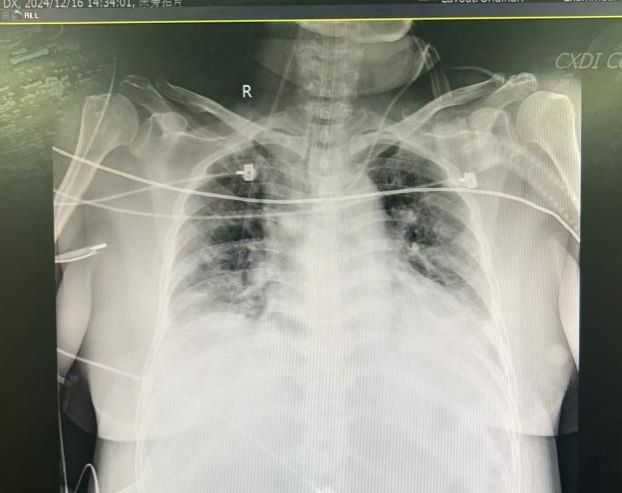

在接下来的治疗中,多学科团队紧密协作,制定个体化治疗方案。在给予抗病毒药物积极治疗甲型流感病毒肺炎同时,对患者进行全面的生命支持和并发症的预防和处理。经过11天的艰苦努力,患者肺功能逐步恢复,胸片肺部阴影明显吸收,各项检验指标趋于正常,成功撤离ECMO,康复治疗10余天后顺利出院。

ECMO上机前 ECMO撤机后